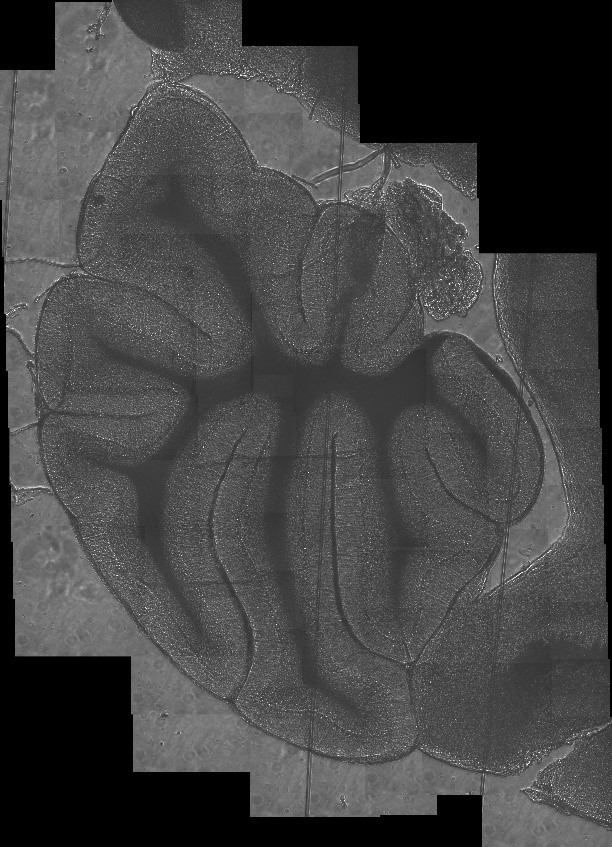

Reconstruction « grand champ » par corrélation de champs individuels d’une coupe sagittale de cortex de rat.

Crédit photo : LESIA